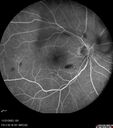

Central Retinal Vein Occlusion - Non-Ischemic - Excellent Outcome17 views57 year old man The right eye has had vision loss for about 3 weeks. He woke up with vision loss.

Medical Hx: HIV . Diabetes Mellitus (since 2014). Thyroid Disease.

Systemic Meds: gemboya. Metformin Hydrochloride. trulicity. losartan. vesepa. Synthroid .

VA OD: sc20/160 OS: sc20/20

TP: OD:14 OS:14

Treated with Avastin

VA 6 weeks later 20/32 – dry one shot.

Missed follow-up after second treatment and came 5 months later with good vision and no macular edemaAug 17, 2025